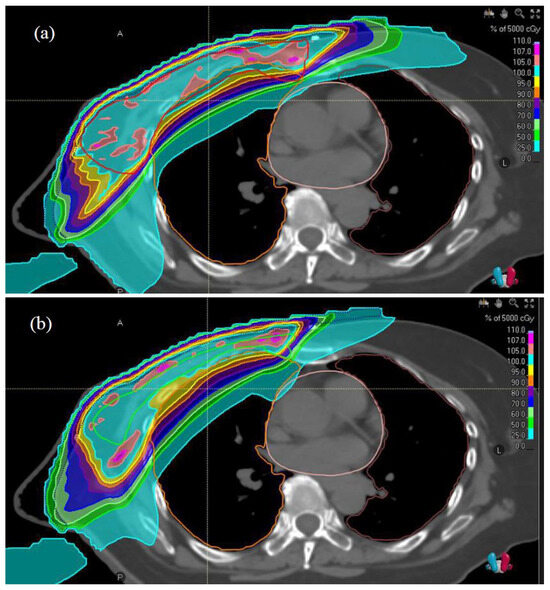

2.3. Treatment Planning